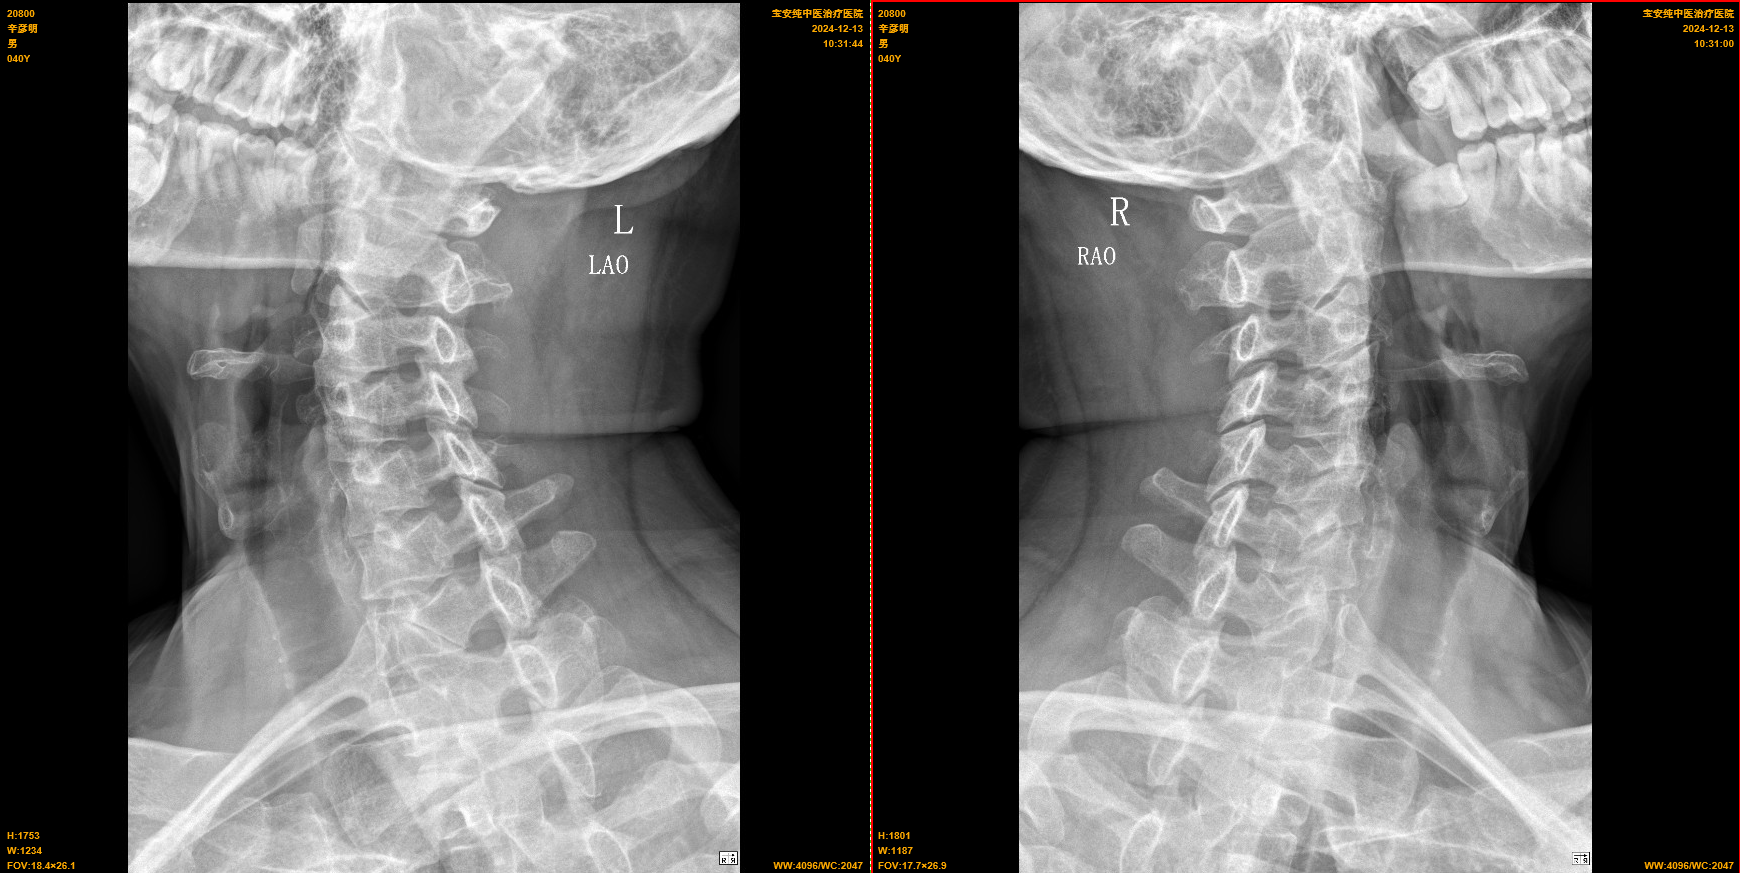

【影像】20241102龙岗骨科医院CT报颈椎曲度变直,C3-6间盘突出(中央型),C6-7间盘突出(右旁中央型),继发椎管狭窄,右侧神经根受压。颈椎X线片报颈椎退行性变。阅片见颈椎向右侧倾,C5-6角折,左侧C3-5椎间孔变小,上位椎体下关节突向后下移位。

【讨论】患者左侧肩胛间区疼痛,仰头加重;左侧椎间孔挤压试验(+),引发左侧肩胛间区疼痛;左侧C4-5椎间孔变小,上位椎体下关节突向后下移位;诊断为神经根型颈椎病。肩胛间区为斜方肌、菱形肌、竖脊肌、上后锯肌所在,查体未见明显肌紧张及条索,基本排除局部肌肉损伤。后仰时左侧肩胛间区疼痛,考虑颈椎刺激肩胛背神经所致。椎间孔挤压试验(+)、X线片见C4-5椎间孔狭窄证实推断正确。

颈椎CT报C3-7间盘突出、C6-7水平椎管狭窄伴右侧神经根受压,因其未引发相应临床症状,故不予诊断。X线片见C5-6角折,颈椎后伸时C5以下椎体不能正常后伸运动,C3-5关节突关节反复超范围后伸而错位,C3-4错位尚未挤压相应神经,C4-5错位刺激C5神经(肩胛背神经)引发肩胛间区及上臂上段疼痛。故治疗时复位C4-5关节突关节治其标,纠正C5-6角折加大C5以下颈椎后伸范围治其本,复位C3-4关节突关节未病先防。